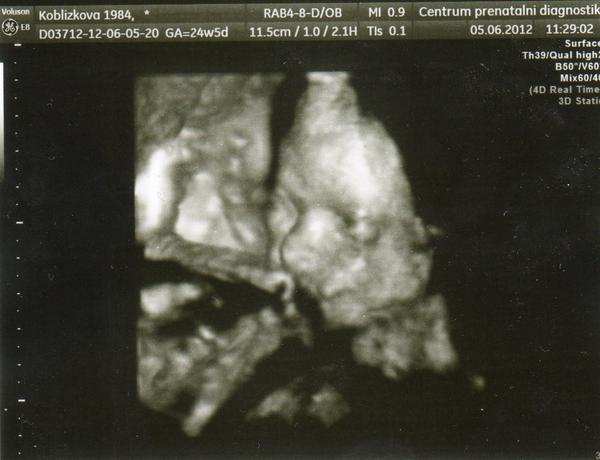

Teda já snad do toho 12.6 nevydržím, moc doufám, že bude všechno v pořádku a bude bít srdíčko 😒

@lennaaa Dr. ví, kam tě poslat. Ty vyšší pracoviště jsou všechny dobrý. A chtěla bys jít i na 4D ultrazvuk?